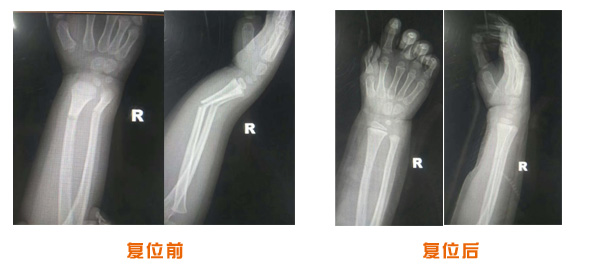

復位前后對比

尺橈骨骨折治療前后